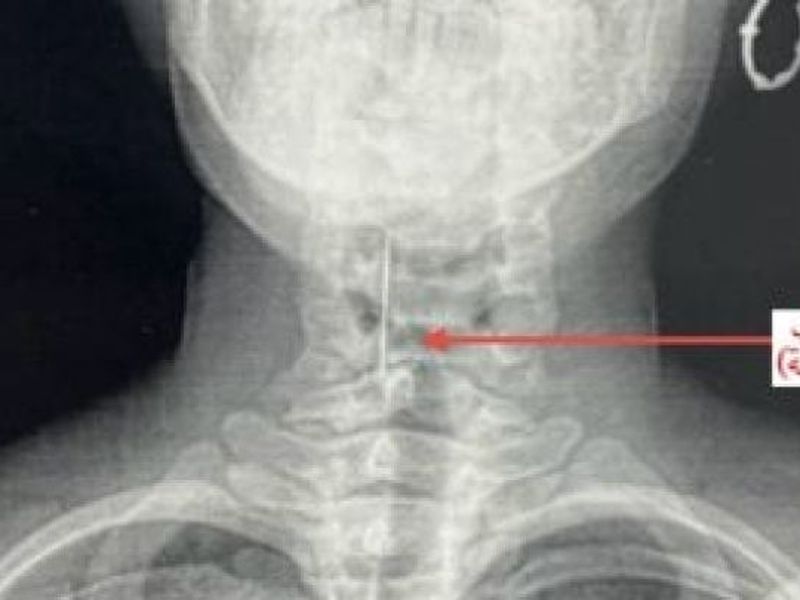

وتابعت المستشفى، أنه على الفور تم إجراء الفحوصات اللازمة والأشعة التي أكدت استقرار "الدبوس" في منطقة دقيقة بمدخل مجرى التنفس، مما شكل خطورة على حياتها.